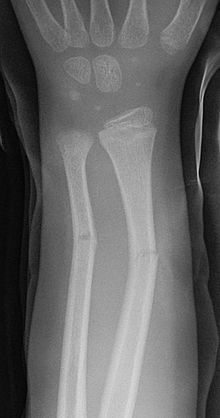

먼저 green stick fracture를 이해하고

기타 골절 수술

5th metatarsal bone fracture

talus fracture

navicular fracture

phalanges fracture